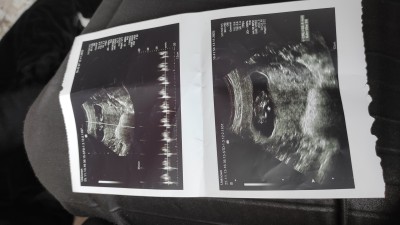

11 haftalık ultrason tahmin veya his paylasin

Gebelik haftası 12+ 3